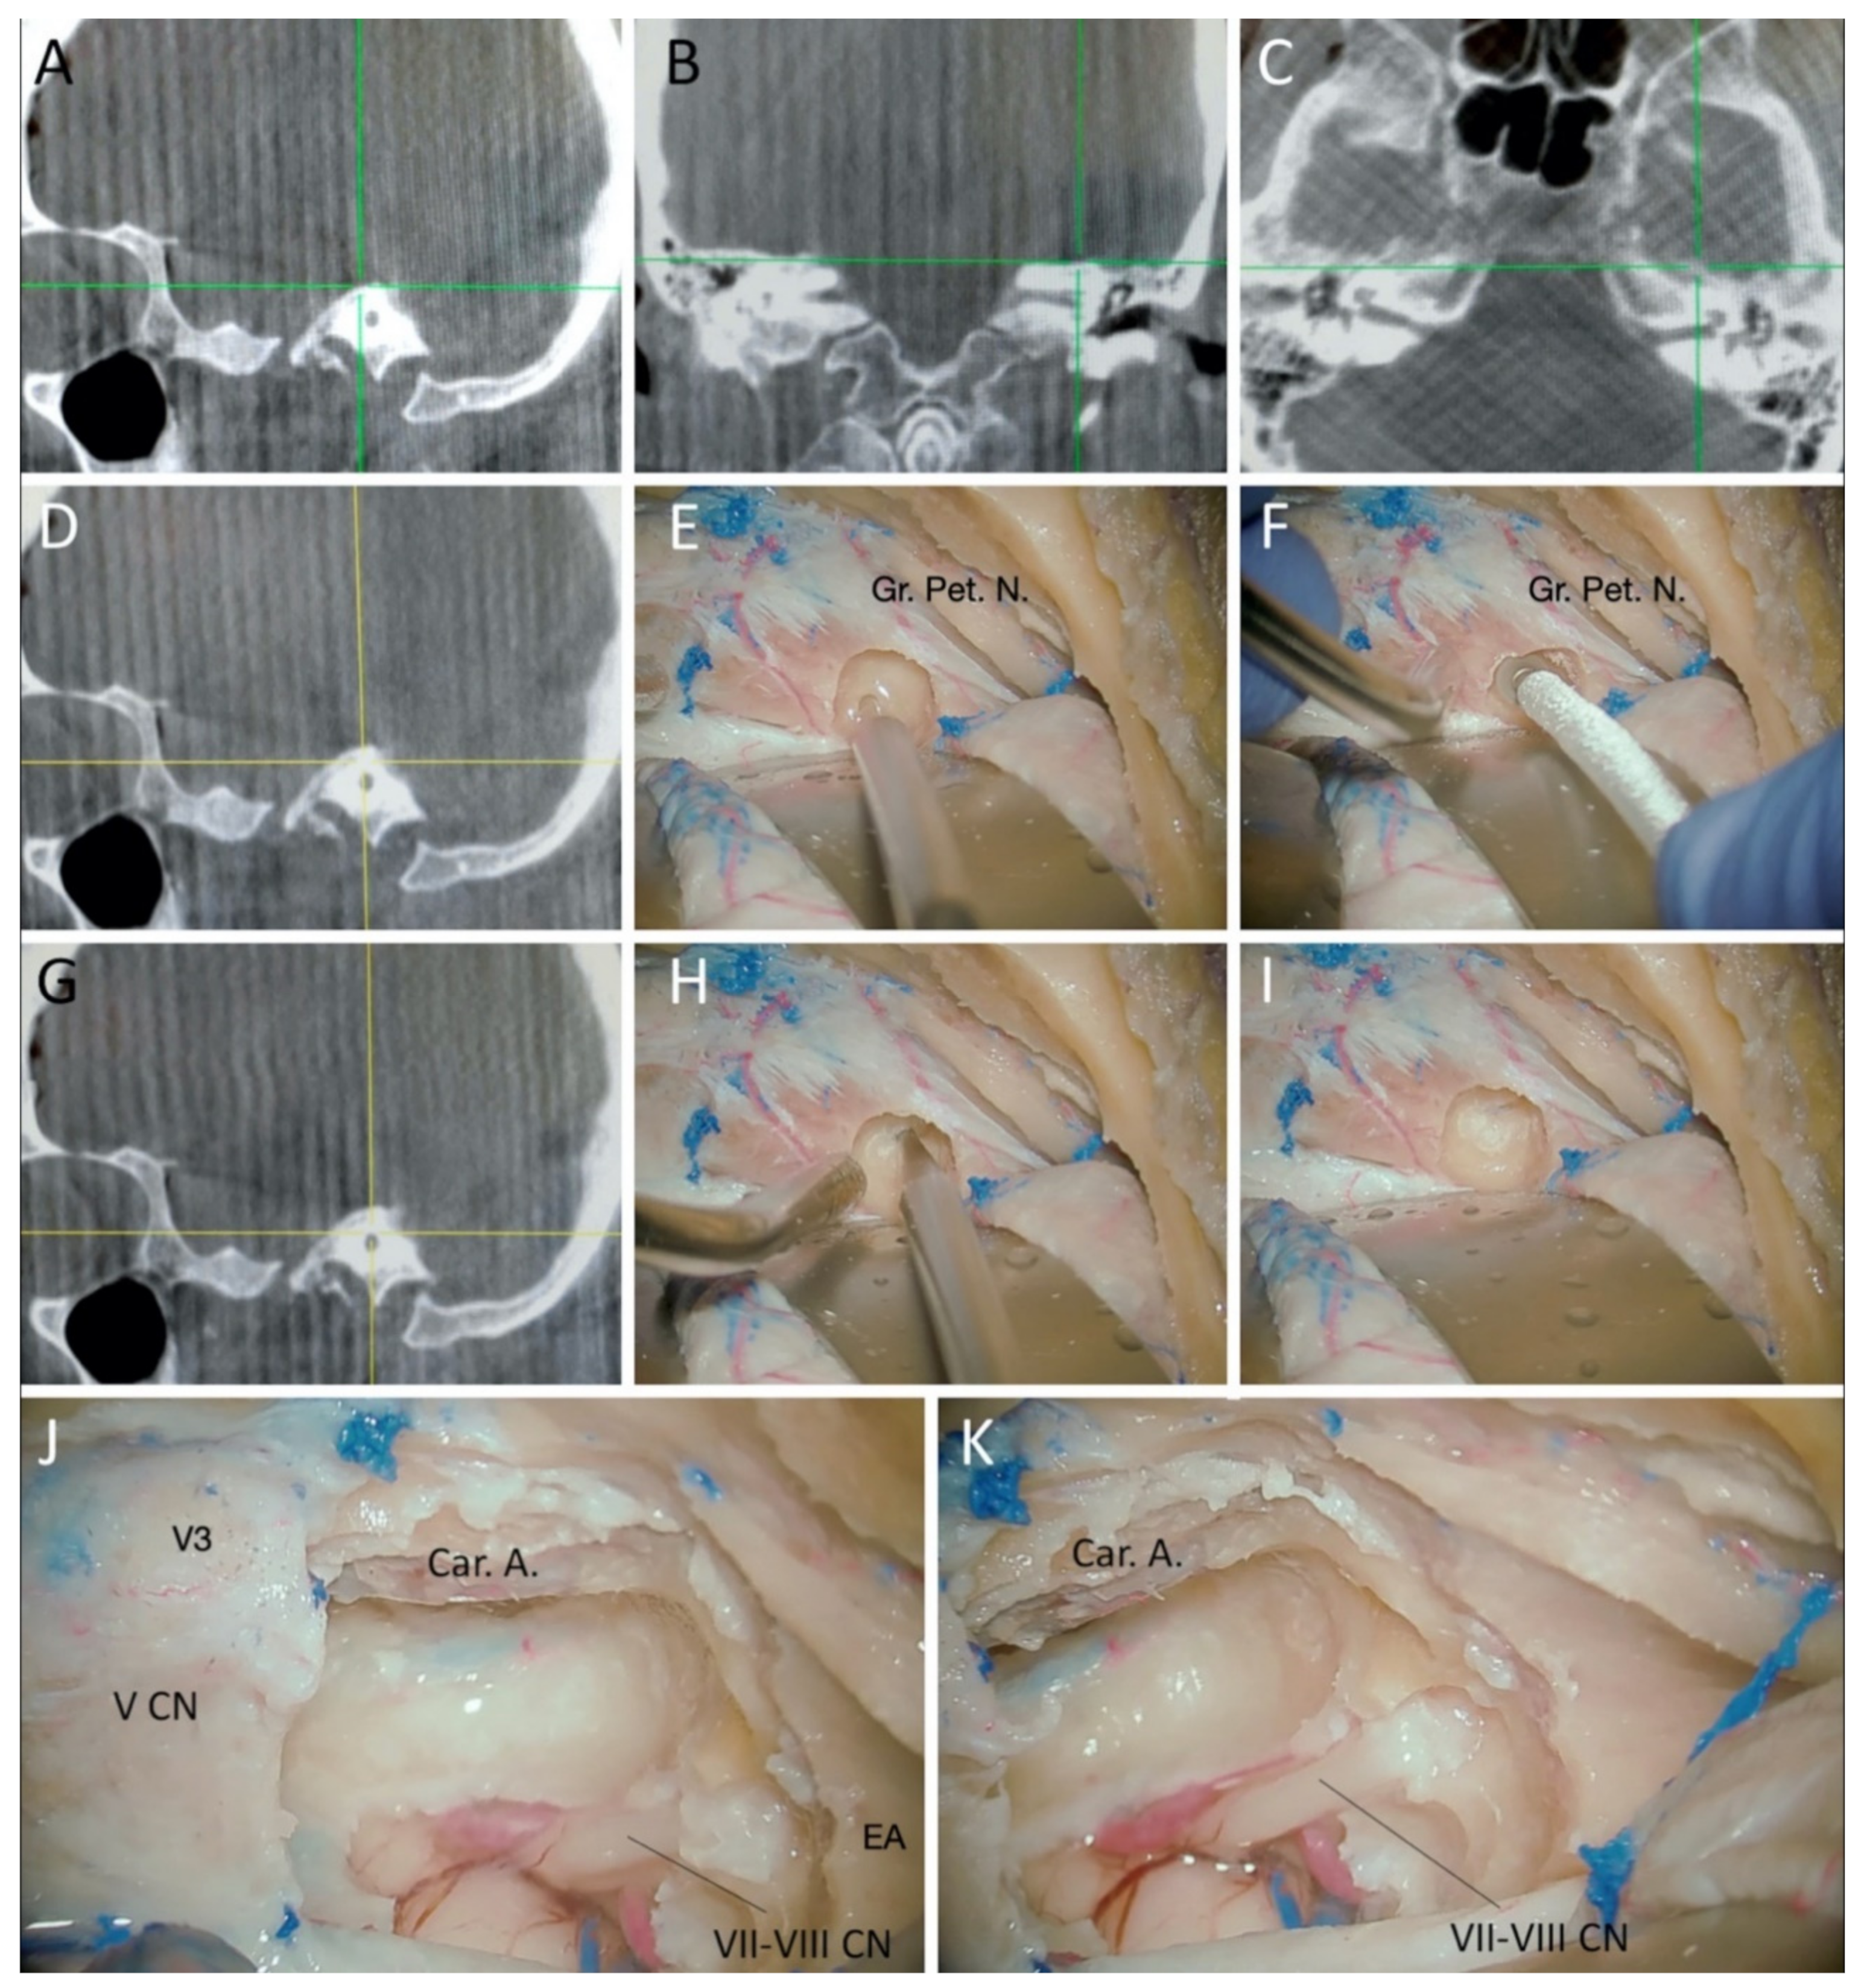

2. Materials and Methods

3.1. Cadaveric Dissection

3.1.1. Surgical Position and Bony Exposure

3.1.2. Craniotomy and Middle Fossa Peeling

3.1.3. Drilling of the Petrous Bone under Neuronavigation